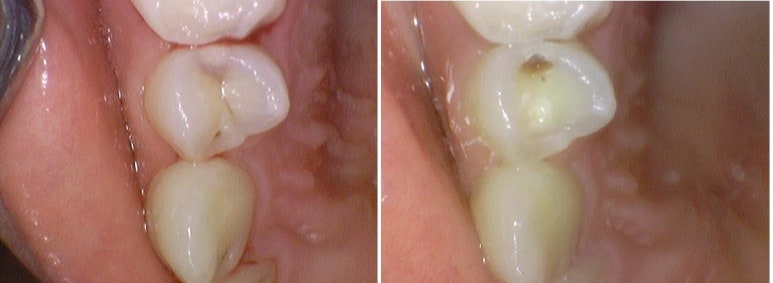

위의 왼쪽 사진에 충치가 없는 것 같으신가요? 치아사이 충치가 있고 치과의사의 눈으로 보면 보이긴 하는데 간혹 충치가 아닌경우도 있어서 더 정확한 판단을 위해서는 엑스레이가 필요합니다.

실제로 엑스레이상에서 충치가 있는것이 확인되었고

충치제거 중 찍은 오른쪽 사진을 보면 충치가 확실히 깊은 있는게 보입니다.

▲이런식으로 오히려 겉에서 보이는 충치보다 사이 충치는 겉에서 까맣게 보이지 않지만 파면 더 깊은 위치에 있습니다.

왼쪽: 겉에서는 보이지 않는 치아사이충치/ 오른쪽: 실제로 치아를 파보면 충치가 깊게 위치하고 있음